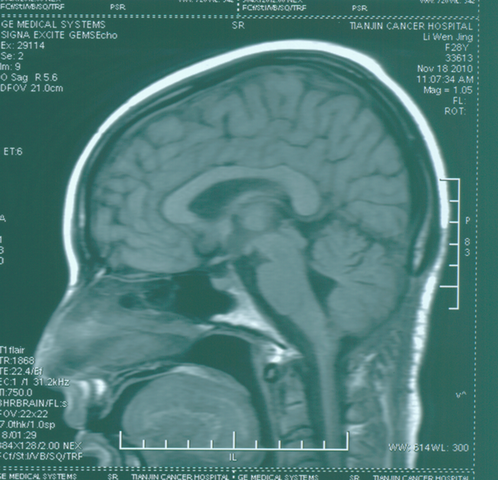

海绵状血管瘤:

手术后